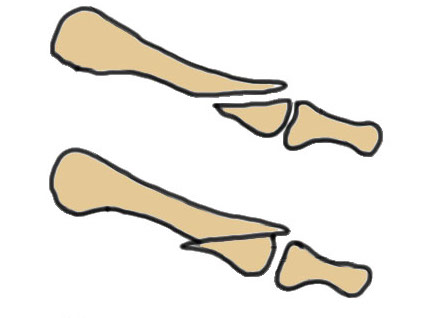

Smillie Classification

Stage 1 - normal xray, MRI positive

| Stage II | Stage III | Stage IV | Stage V |

Slight widening of joint space Sclerosis of epiphysis |

Flattening of epiphysis

|

Fragmentation of epiphysis Multiple loose bodies |

Osteoarthritis |